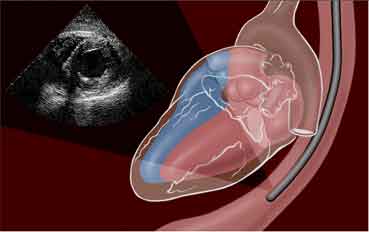

Since the lower end of esophagus just hugs the left atrium , this anatomical concept was successfully exploited for imaging heart in TEE.Now cardiac anesthetists routinely use the esophagus as an imaging port during complex mitral valve surgeries.

Note , the esophagus does a friendly hug as it crosses the heart posteriorly .It is a perfect anatomical sense , to Image and pace the heart from within the esophagus !